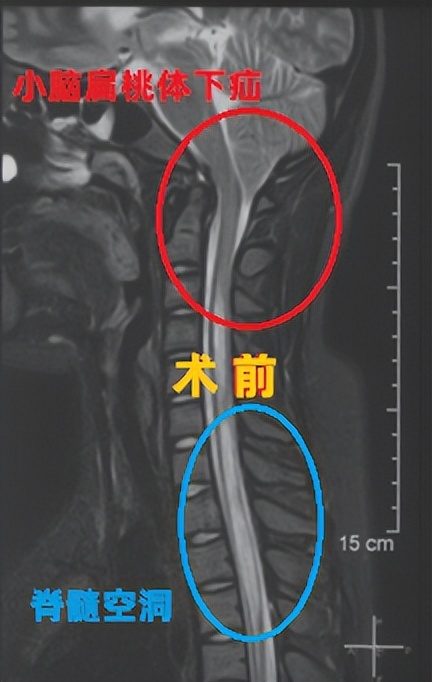

术前影像学资料:

萱萱的情况还是比较严重的,不仅出现小脑扁桃体下疝,还出现了长节段的脊髓空洞,再发展下去很可能会出现一些肢体或躯干的感觉、运动症状,需要尽快处理。经过周详的术前讨论,最后王作伟主任团队决定给萱萱进行“后颅窝减压+小脑扁桃体部分切除术”。